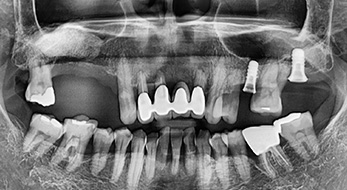

모의수술을 통해 맞춤형 수술 유도장치를 제작하여 비절개로 임플란트를 식립하기 때문에 통증을 줄이고 회복 속도를 높인 컴퓨터분석을 이용한 임플란트로 부담을 줄여드립니다.

개인의 잇몸 라인에 맞게 상부 기둥을 맞춤 제작하는 방법으로 자연스러운 잇몸라인은 물론

이물질 침투가 어렵기 때문에 건강한 임플란트 관리에 용이합니다.

임플란트 식립 전, 임플란트가 심겨질 잇몸 건강 상태를 회복시킨 후에 임플란트를 식립합니다.

때문에 오래 사용할 수 있는 임플란트 치료가 가능합니다.